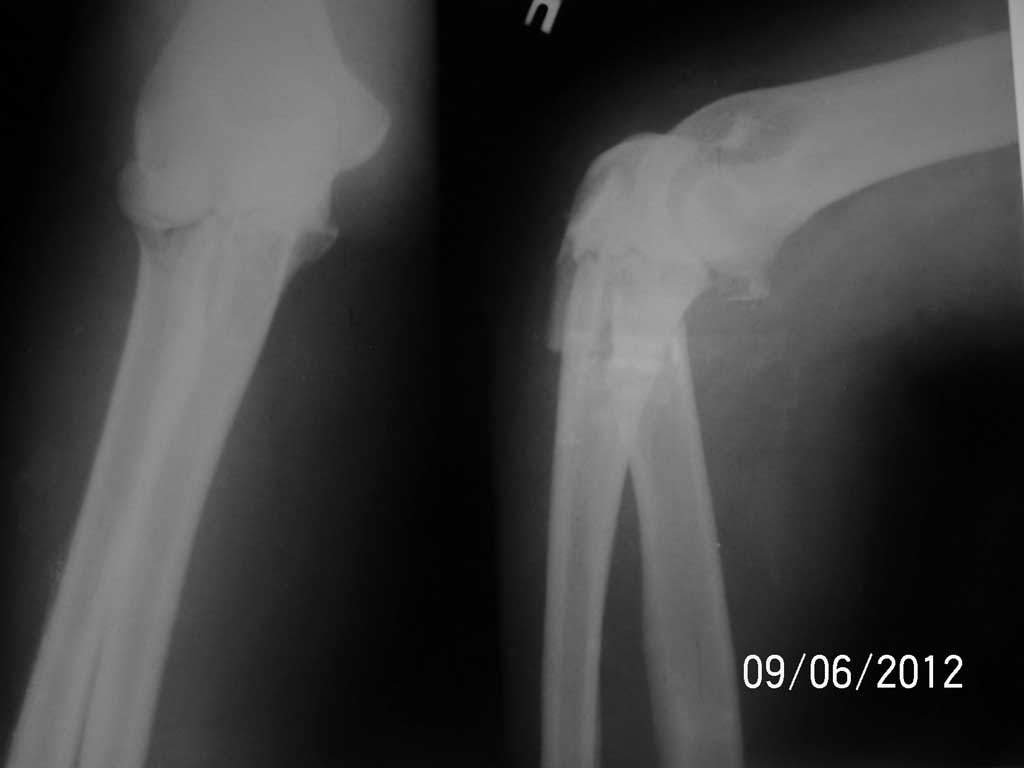

Доброго времени суток! Мне показалось, или на Ro-граммах перелом проксимального луча?

Конечно качество R-гр оставляет желать лучшего,но создается впечатление,что перелом оскольчатый и к тому же внутрисуставной,поэтому считаю открытый остеосинтез пластиной в данном случае оптимальным. Если же ошибаюсь можно попробовать и штифт. Что касается остеосинтеза по Веберу, то в данной ситуации считаю его нецелесообразным. Как раз недавно почти подряд прошло два похожих случая с гипертрофическими ложными суставами на фоне похожих переломов и их остеосинтеза по Веберу. Желаю удачи в принятии решения. Поделитесь потом результатами.

Насколько дальше распространяется линия перелома? Не могли бы выложить снимки в лучшем качестве?

PS Неплохо бы еще КТ сделать, тогда вопросы по поводу выбора металлоконструкции видимо отпали бы.